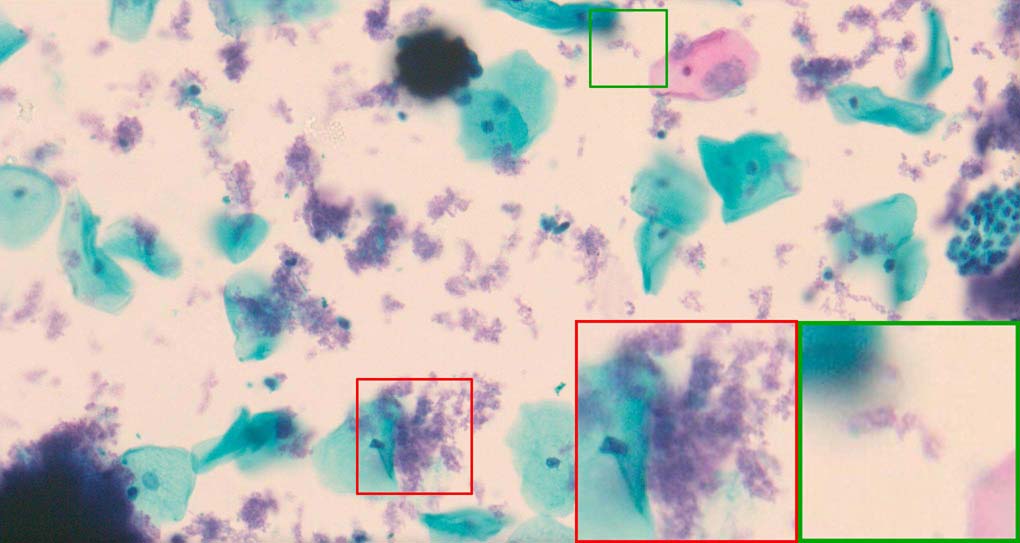

A good image fusion method should contain the following properties. First, it preserves both the details of small size objects and the integrity information of large size objects in the fused image, even in the case of the size of the interested objects varying largely in the image. For example, the cervical cell images from the microscope contain both small size isolated cells and large size agglomerates, which are both useful for cervical cytology [5]. Second, it should be efficient enough to handle large-scale data. For instance, it needs to process thousands of fields of view (FoV) in an acceptable time for the whole slide scanning in digital cytopathology [6], which requires to fuse a series of high resolution images captured at each FoV in a very efficient way. Third, it does not produce obvious artifacts. Despite being studied extensively, to our best knowledge, existing fusion methods may not meet these requirements simultaneously.

To demonstrate the effectiveness and efficiency of the proposed image fusion method , we conduct a set of comparative experiments on three image datasets. The first is composed by 8 pairs of multi-modal medical images and the second one contains 15 pairs of multi-focus gray or color natural images. These two datasets are often used in many related papers and some examples are shown in Figure 3(a) and Figure 3(b). The third one is a new multi-focus cervical cell image dataset collected by ourselves, which consists of 15 groups of color images and each group contains a series of multi-focus cervix cell images with size of or , etc. Some source examples are shown in Figure 3(c). Our source code implemented in C++ along with the new multi-focus cervical cell image dataset is available online.

Figure 9, Figure 10 and Figure 11 show the comparative fused results of the multi-focus cell images shown in Figure 3(c). For clarity, we also present a closeup view in the right-bottom of each sub-picture in Figure 9 and Figure 10. As shown in the close-up views of Figure 9, the fused images based on DSIFT, IM, MWGF and BF methods are extremely blurred in the boundary and fail to keep the details of cell nucleus. Furthermore, the DTCWT and NSCT based methods produce halo artifacts in the fused images, while GFF and CNN based methods fail to preserve the small cell nucleus. LP-SR based method nearly works fine which keeps the most of the details of the small size cells, but the integrity of the clustered large size cells is damaged. Fortunately, in our proposed method, the integrity of the clustered large size cells is preserved and most of the isolated small size cells are maintained from the original images, which demonstrates the best visual quality.

Similarly, as shown in the close-up views of Figure 10, the fused images from DSIFT, IM, MWGF and BF are blurred and lose some nucleus details, while the results from DTCWT, GFF, CNN and NSCT produce halo artifacts. LP-SR based method can keep details well but also produces halo artifacts and other noise. Our method can preserve the focused areas of different source images well without introducing any artifacts. For the example illustrated in Figure 11, the fused images generated by DSIFT, DTCWT, IM and NSCT all fail to preserve the focused areas of different source images and result in extremely blurred images. The GFF, CNN, MWGF and BF based method introduces a lot of color distortion of the nucleus regions and the obvious halo artifact. The result of LP-SR based method is close to the one of our method but introduces some odd color distortion. Again, our method produces fused image which can preserve the focused areas of different source images well without introducing any artifacts.